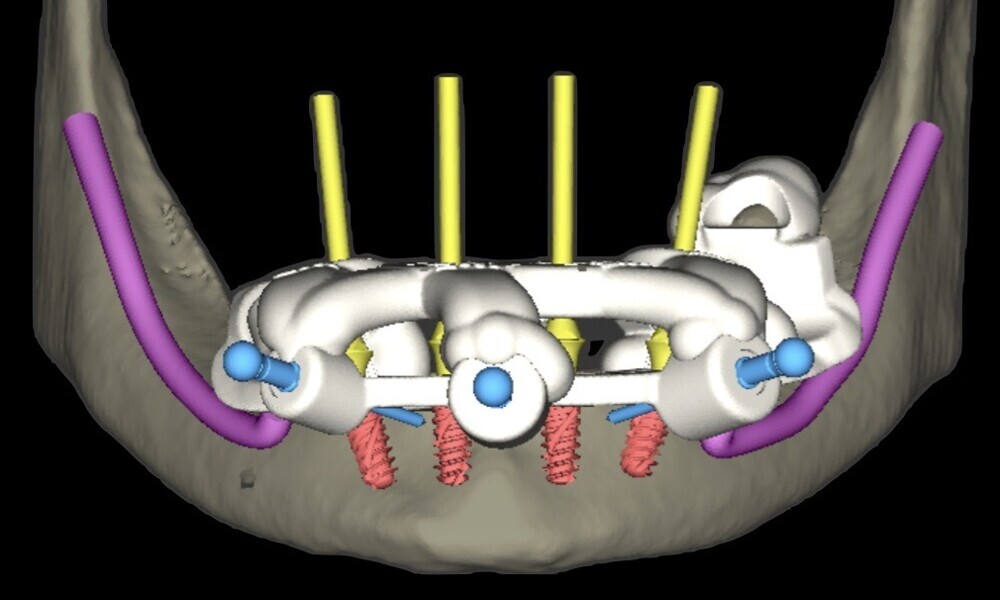

To ensure precise and predictable treatment planning, the DICOM files, STL files and clinical photographs were seamlessly integrated into Smilecloud, utilising advanced artificial intelligence technologies to deliver a highly personalised smile with exceptional precision (Figs. 11–15).

Figs. 11–15: DICOM files, STL files and clinical photographs were integrated into Smilecloud, leveraging artificial intelligence for precise, personalised smile design.

planning of implant positioning (18–21);

Figs. 16–28: The treatment workflow included the extraction of hopeless teeth, implant planning and positioning, and surgical guide fabrication.

Fig. 18

Fig. 19

Fig. 20

Fig. 21